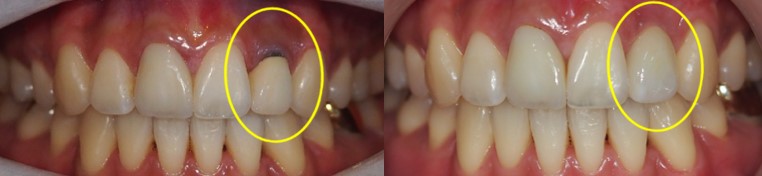

▲ 치료 전 구강 사진 ▲ 치료 후 구강 사진

#22 치아는 전후 차이가 느껴지실까요?

이렇게 본래 치아였던 것처럼 말끔한 구강 상태를 확인할 수 있습니다.